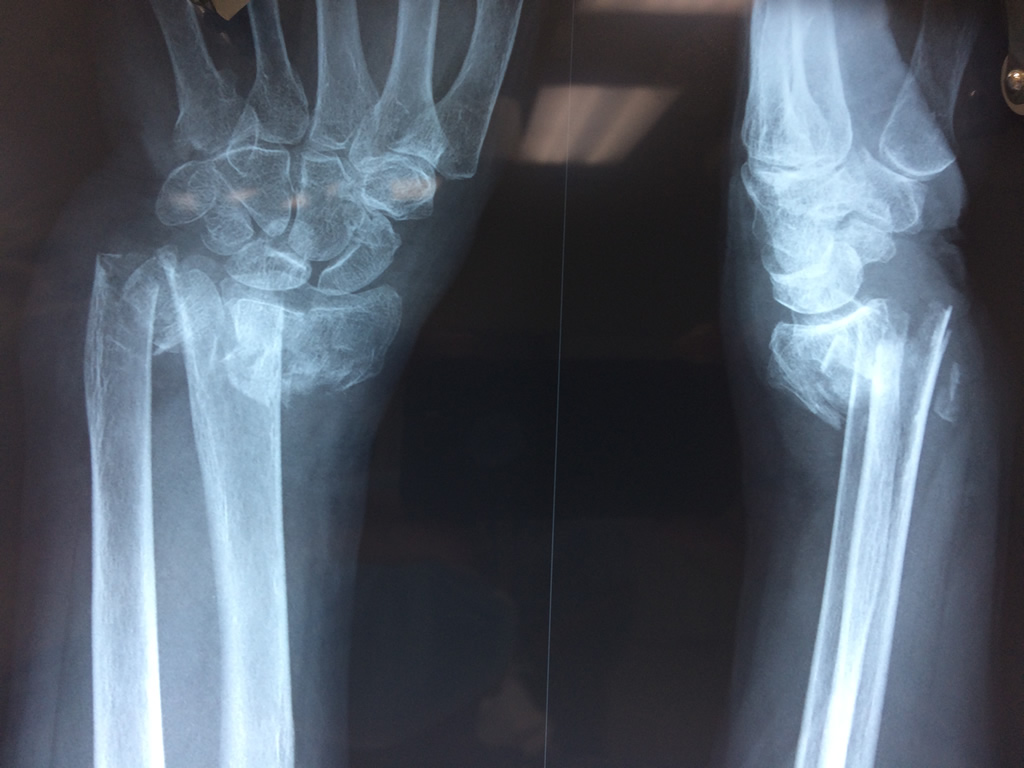

Cirugía de Fémur - Cirugías de Muñecas y Manos

Los procedimientos más comunes en cirugía de la mano son aquellos destinados a reparar traumatismos, incluyendo lesiones de tendones, nervios, vasos sanguíneos, y articulaciones; huesos fracturados; y quemaduras, cortes, y otros daños de la piel.